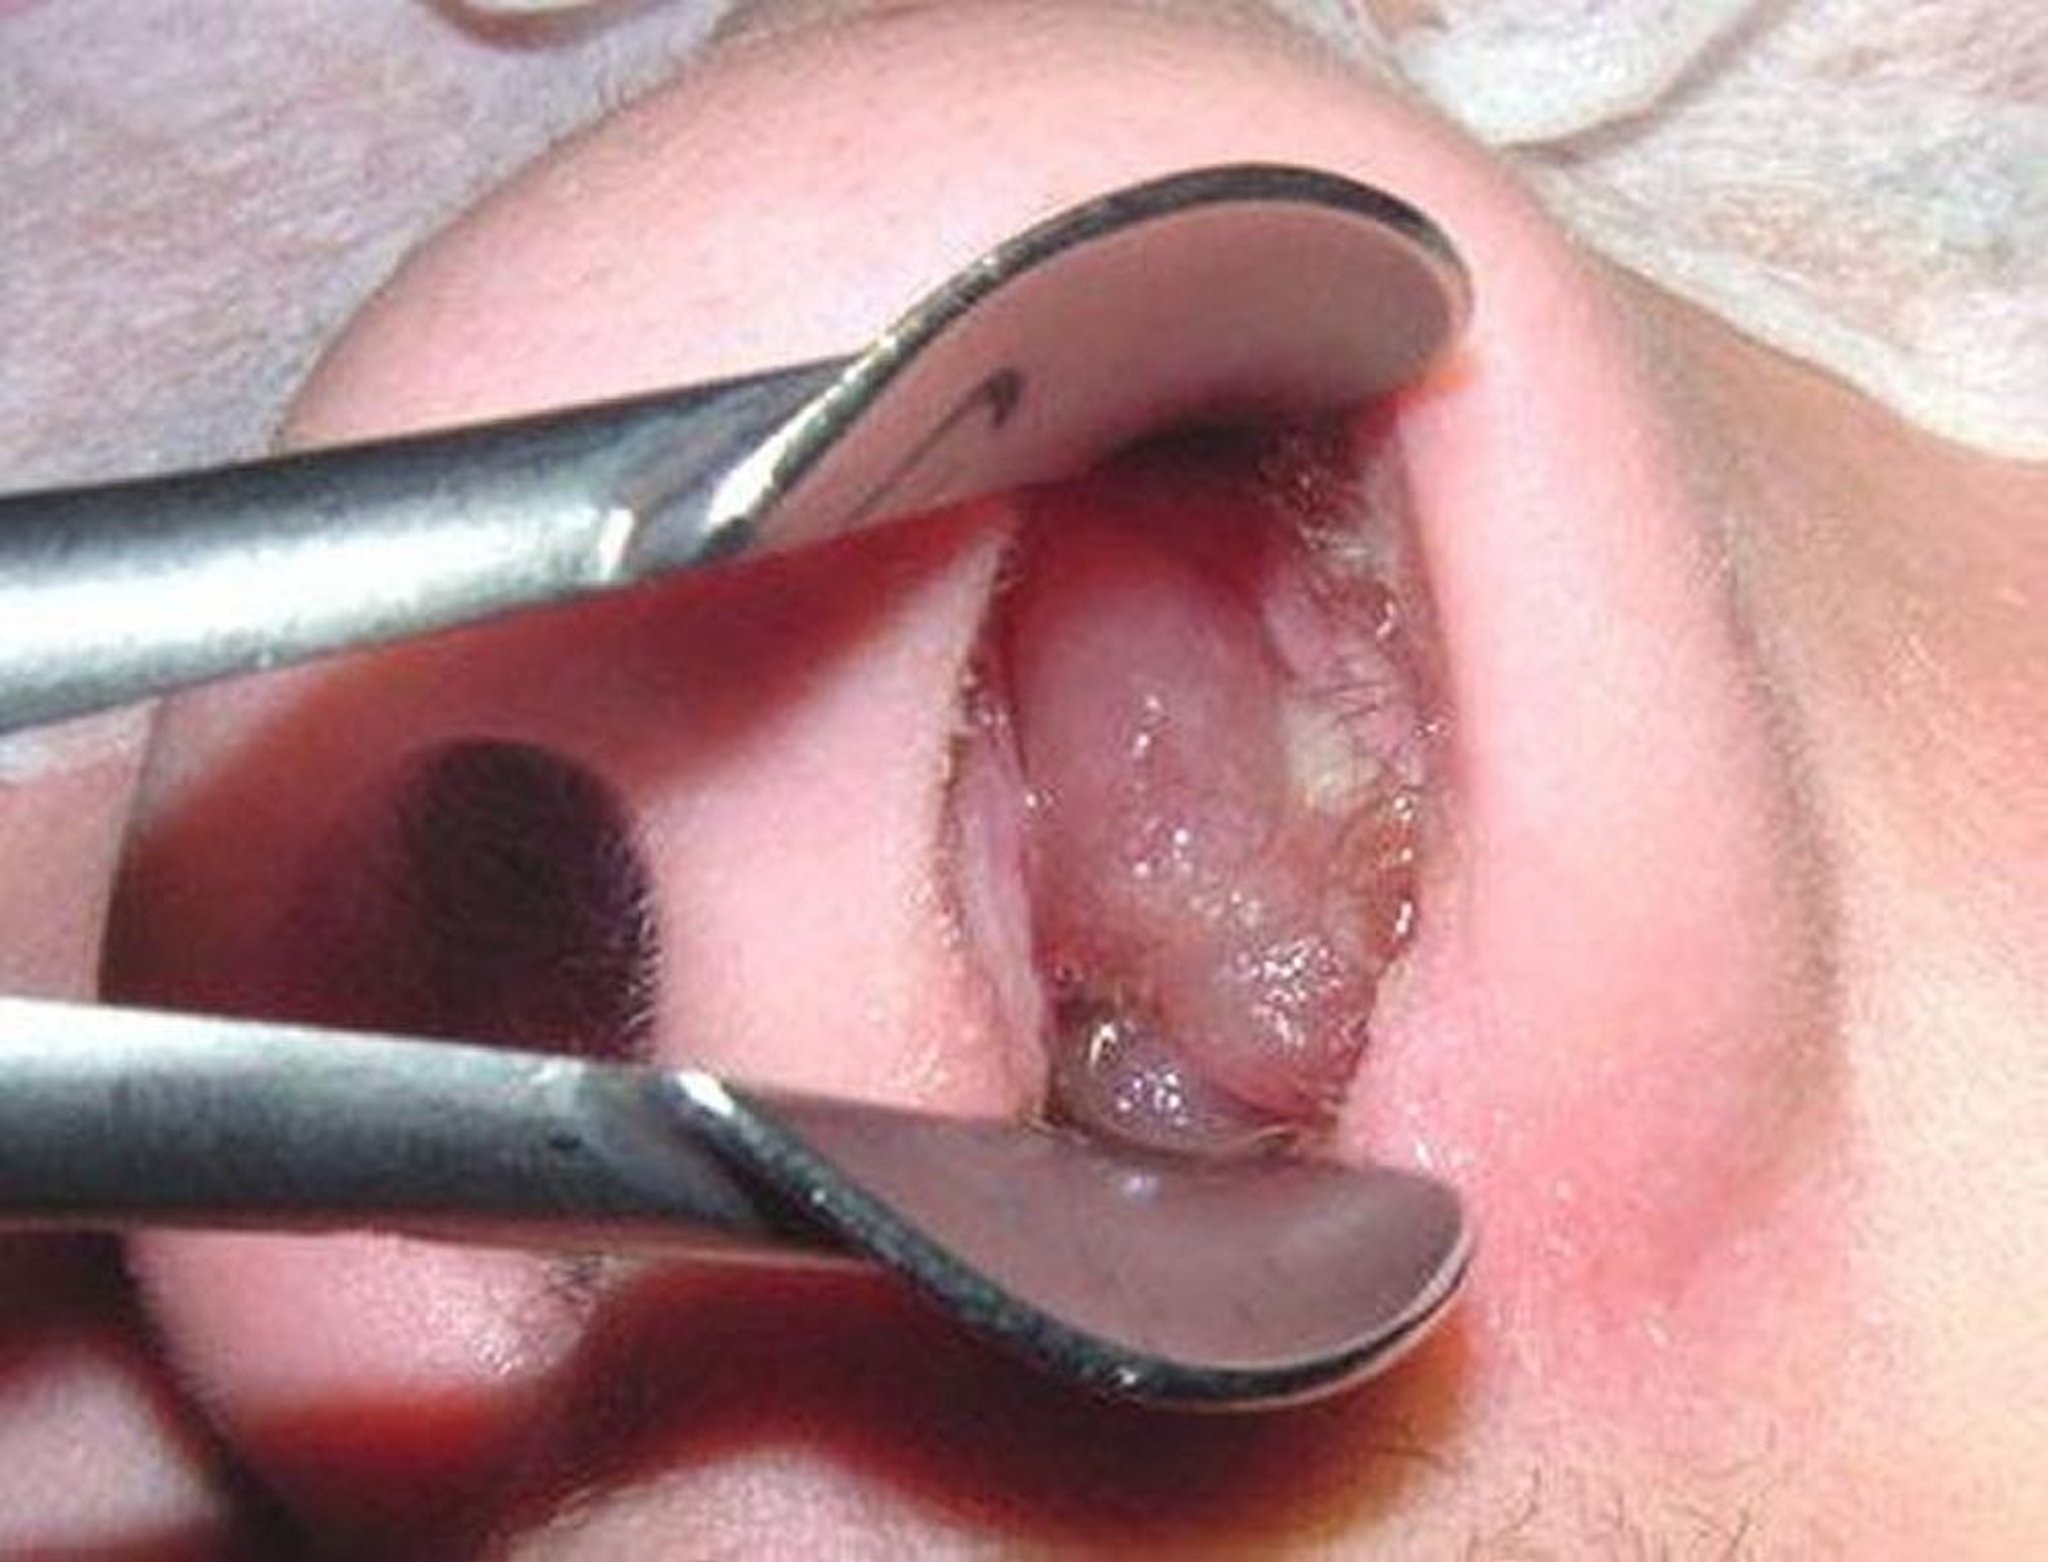

Polip hidung adalah daging tumbuh berbentuk tetesan yang terbentuk di sekitar bukaan rongga sinus dan di dalam hidung. Polip matang menyerupai buah anggur yang dikupas dan tidak berbiji. Tidak seperti polip dalam usus besar atau kandung kemih, polip dalam hidung bukanlah tumor dan tidak menunjukkan peningkatan risiko kanker. Gejala tersebut hanyalah cerminan dari peradangan, meskipun mungkin ada riwayat keluarga yang mengalami masalah tersebut.

Polip hidung matang dapat menyerupai anggur tanpa biji yang dikupas.

Gambar disediakan oleh Bechara Ghorayeb, MD.